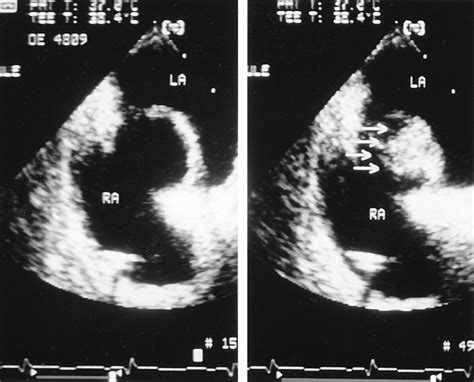

• Echocardiogram: This is a non-invasive test that uses sound waves to create images of the heart. A transesophageal echocardiogram (TEE) is often used to get a clearer view of the heart's structures.

• Bubble Study: During an echocardiogram, a saline solution with microbubbles is injected into a vein. If the bubbles appear in the left atrium, it indicates the presence of a PFO.